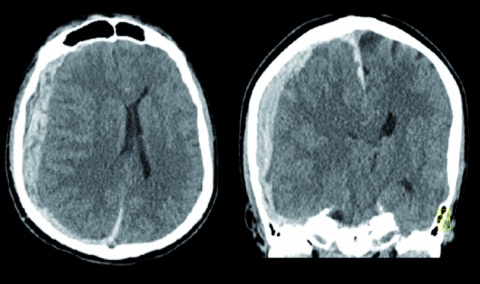

Der erste CT-Scan des Schädels im Schockraum der Zielklinik zeigte ein akutes Subduralhämatom über der gesamten rechten Hemisphäre, im Interhemisphärenspalt sowie auf dem Tentorium mit einer Breite von etwa 18 mm. Korrespondierend zeigte sich eine Mittellinienverlagerung mit einer subfalcinen und tentoriellen Hernierung und deutlich eingeengten basale Zisternen (Abbildung 2). Es erfolgte eine Notfalloperation mit Entlastungskraniotomie der rechten Hemisphäre und Hämatom-aus-räumung.